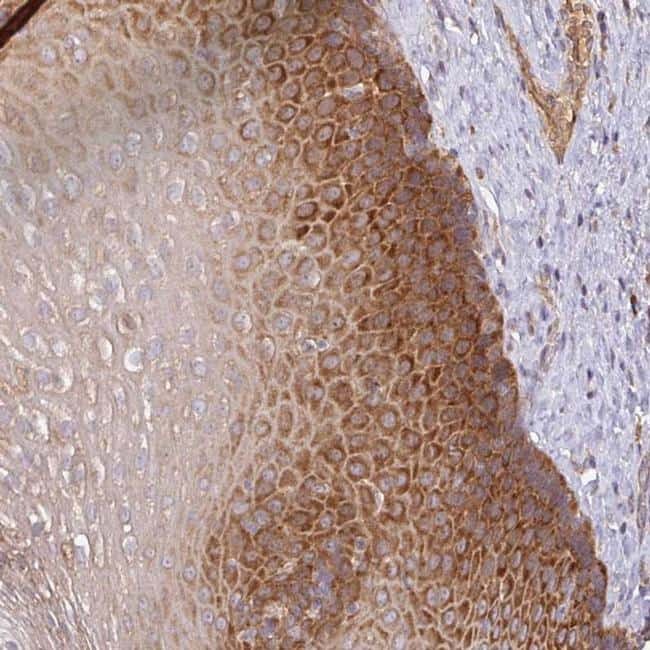

- Main image

- Experimental details

- Immunohistochemical analysis of GALP in human esophagus using GALP Polyclonal Antibody (Product # PA5-62877) shows strong cytoplasmic positivity in squamous epithelial cells.